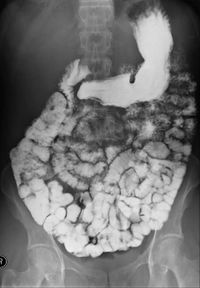

مثال على المادة المظللة في الأمعاء الدقيقة، لاحظ أنه لولا المادة المظللة ماظهر باطن الأمعاء

مركبات الباريوم (أيضاً من المواد المظللة الممتصة) ومثالها: سلفات الباريوم، والتي يتم حلها بالماء، ثم شربها، هذه المركبات لا تتحلل ولا يتم امتصاصها من قبل الأمعاء، مما يجعلها ملائمة لإظهار مجاري الجهاز الهضمي ومثالها ظاهر في الصورة. المواد المظللة من نوعية الباريوم تنشط حركة الأمعاء، هذه الخاصية تفسِّر استخدام هذه المواد أيضا كعلاج أو محاولة علاج الإنسداد المعوي، وهناك فائدة أخرى، وهي إمكان مراقبة نتائج هذه المحاولة العلاجية باستخدام الأشعة.